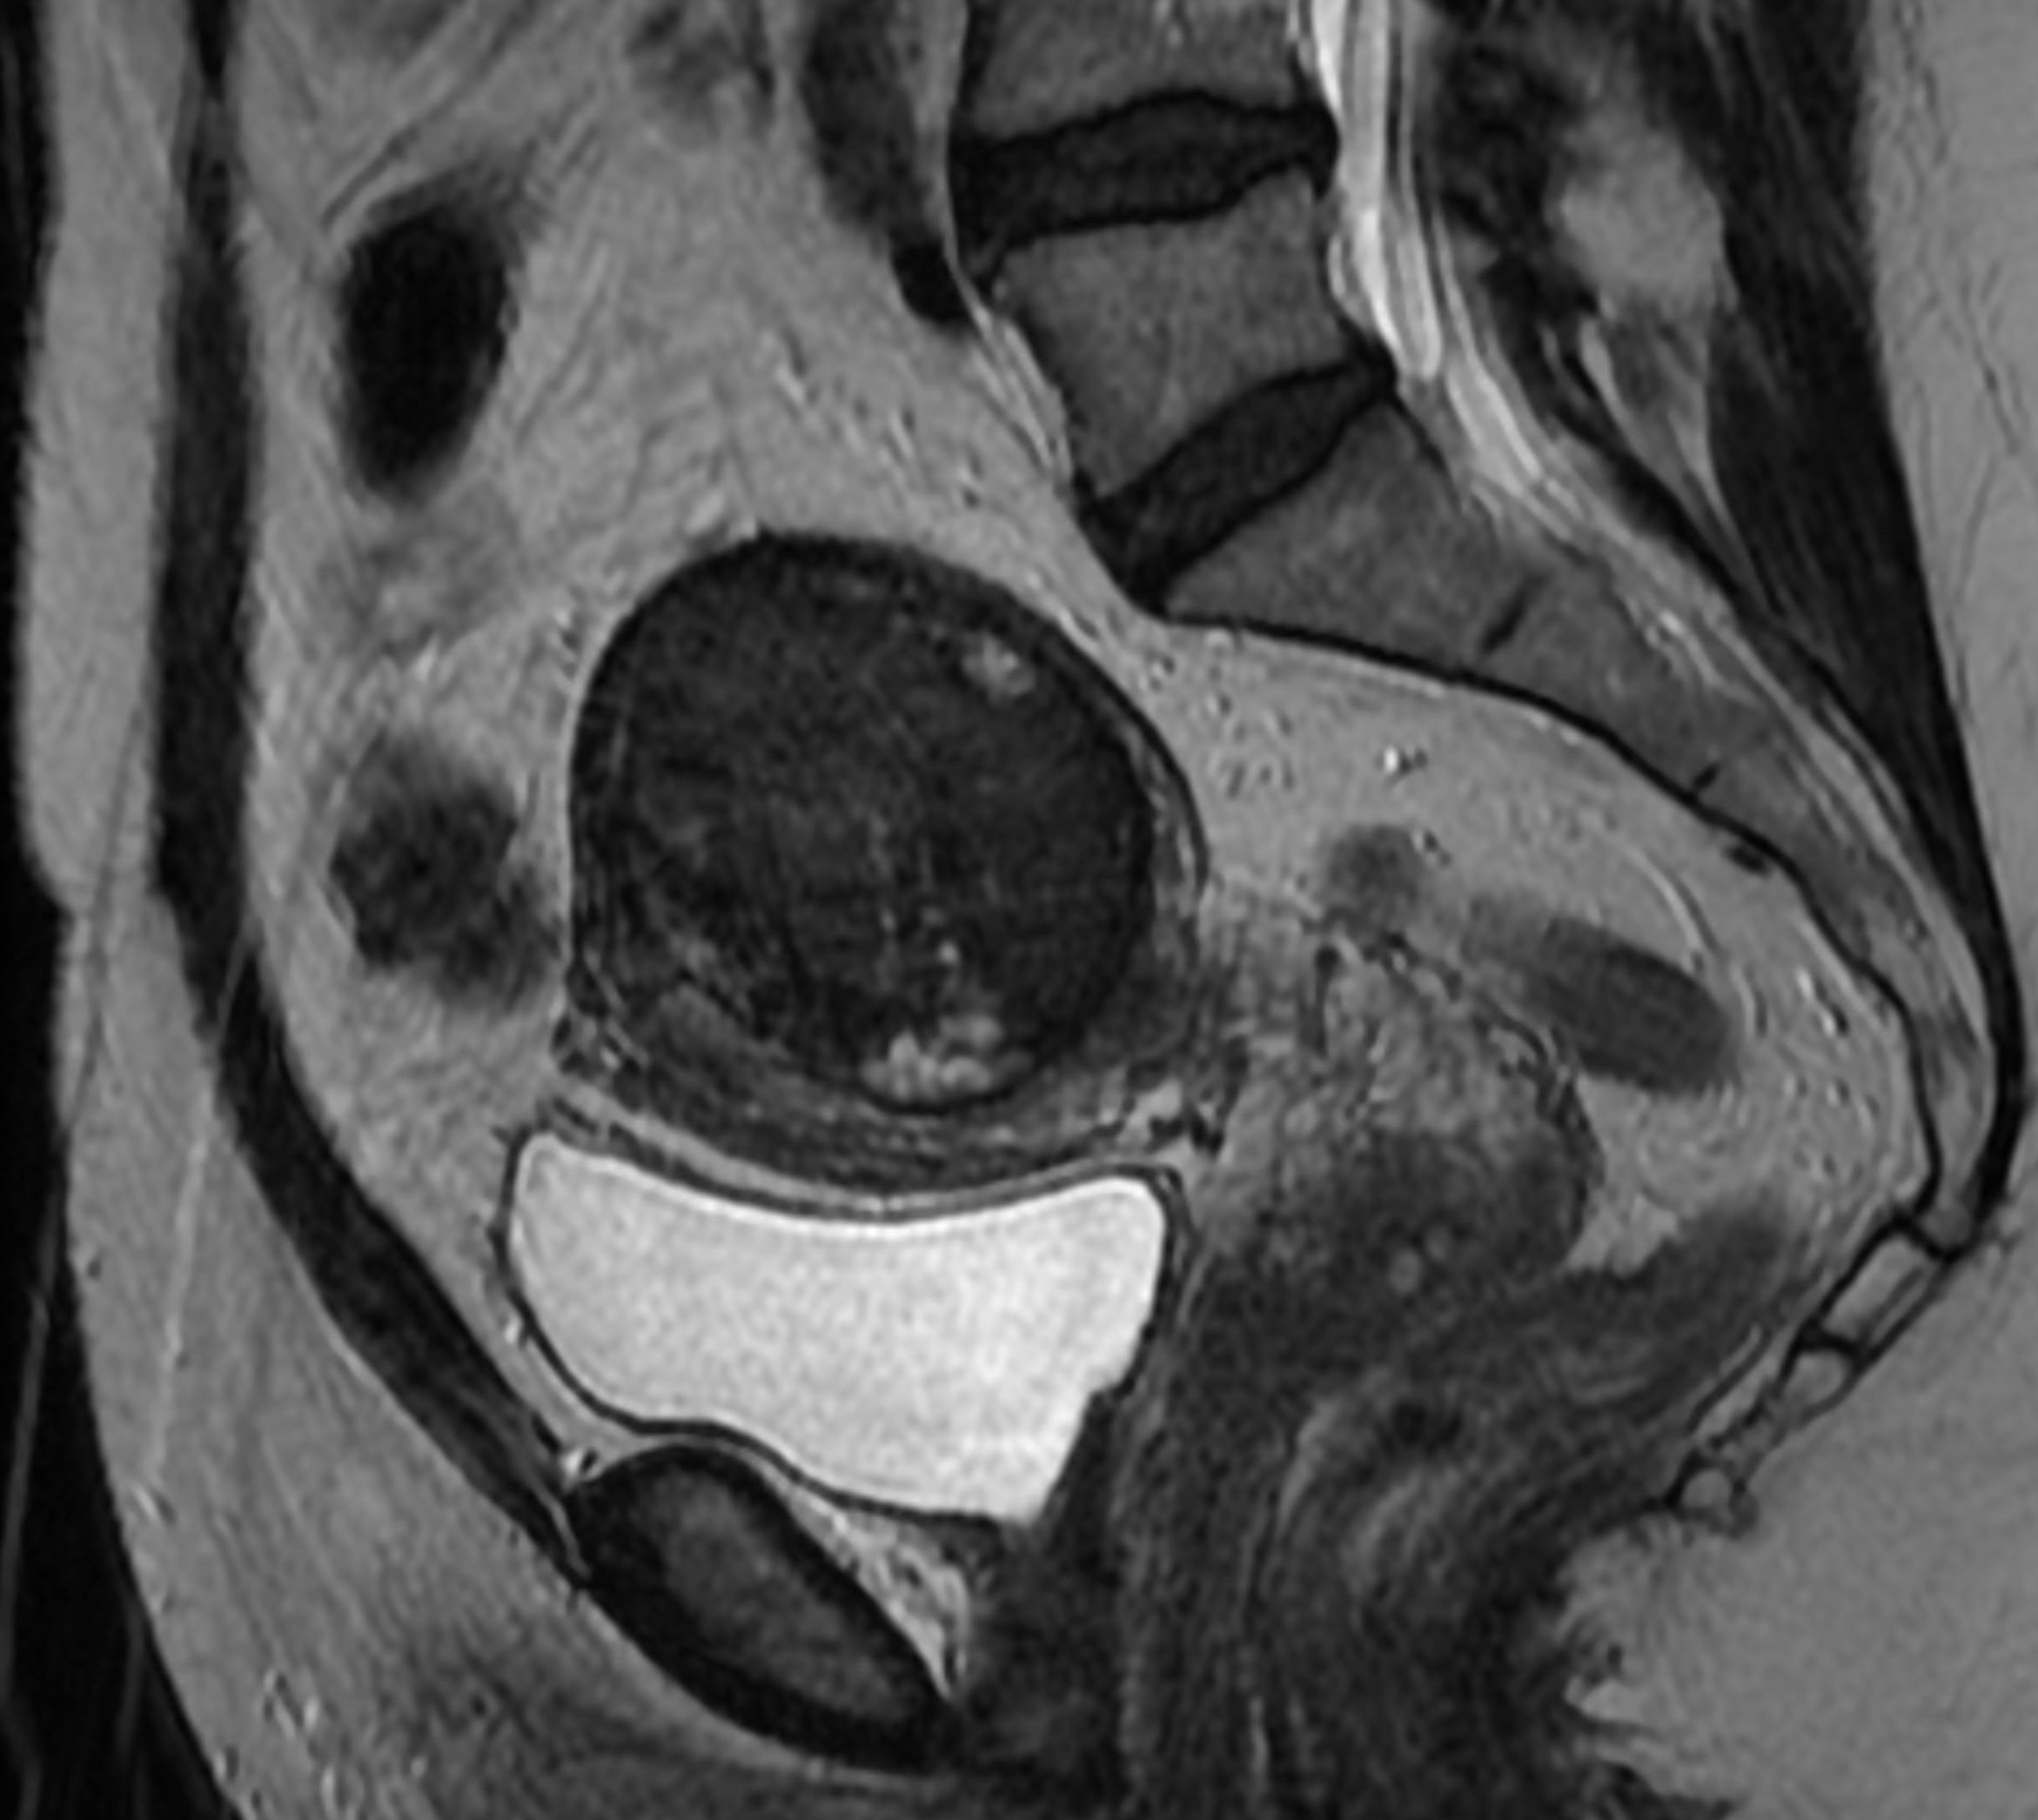

Uterine Fibroid Embolization